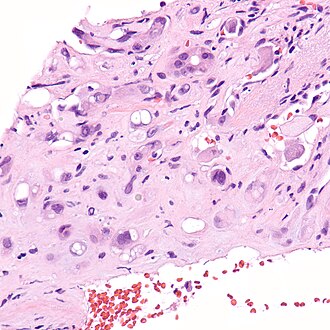

Epithelioid hemangioendothelioma. H&E stain. | |

| LM | large epithelioid perivascular cells with abundant pale eosinophilic cytoplasm and cytoplasmic vacuolation ("blister cells") - may form lumen and have RBC within, vesicular nucleus +/-prominent nucleolus; tuft-like projections into capillaries; cells may be in well-circumscribed paucicellular nodules or poorly formed cellular aggregates |

- Large epithelioid perivascular cells with:

- Abundant pale eosinophilic cytoplasm.

- Cytoplasmic vacuolation (some cells) - AKA "blister cells" - key feature.

- May form lumen and have RBC within.

- Vesicular nucleus with prominent nucleolus in some cells.

- Tuft-like projections into capillaries.

- Tumour cells may be in well-circumscribed paucicellular nodules or more cellular poorly formed aggregates.